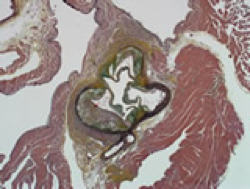

Atherosclerosis is a disease that begins with the invasion and accumulation of white blood cells, or foam cells, onto artery walls. The thickening of the artery walls results in proliferation of intimal-smooth-muscle cell creating an atheromatous plaque. This build up, while usually staying asymptomatic for years or even decades, can eventually lead to thromboembolisms, coronary thrombosis, strokes, heart attacks and/or infarction.

- The effects of a test article on aortic plaque formation and lipidemia may be investigated using either a progression or regression study in ApoE or other mutant mice fed a high fat diet. Mice are placed on the diet from 6-16 weeks and the test article is administered. End points include blood lipids, cholesterol, and triglycerides, as well the assessment of formation of plaque (plaque burden) in the aortic sinus. Assessment of plaque may be conducted using a Paigen type method with histomorphometry.

Look to CBI for validated models for the assessment of atherosclerosis and hyperlipidemia, including progression and regression studies. Assessment of plaque may be conducted using a Paigen type method with histomorphometry.